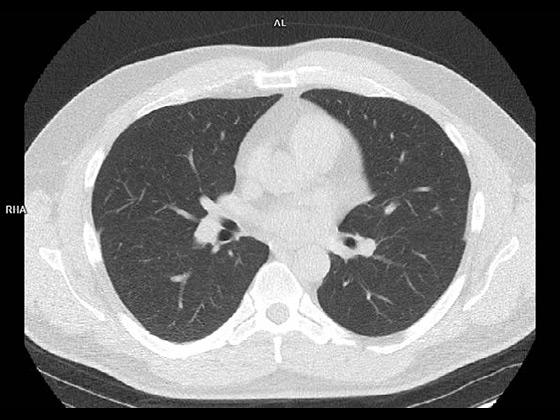

With a mobile lung cancer screening program, you can bring the low-dose CT exam that at-risk patients need closer to where they live. With a short set-up, our self-contained Mobile Lung Screening Solution with a SOMATOM go.Up CT scanner offers the high image quality, ease of use, and flexibility you need to create a lung screening program that meets the real-life needs of your community.